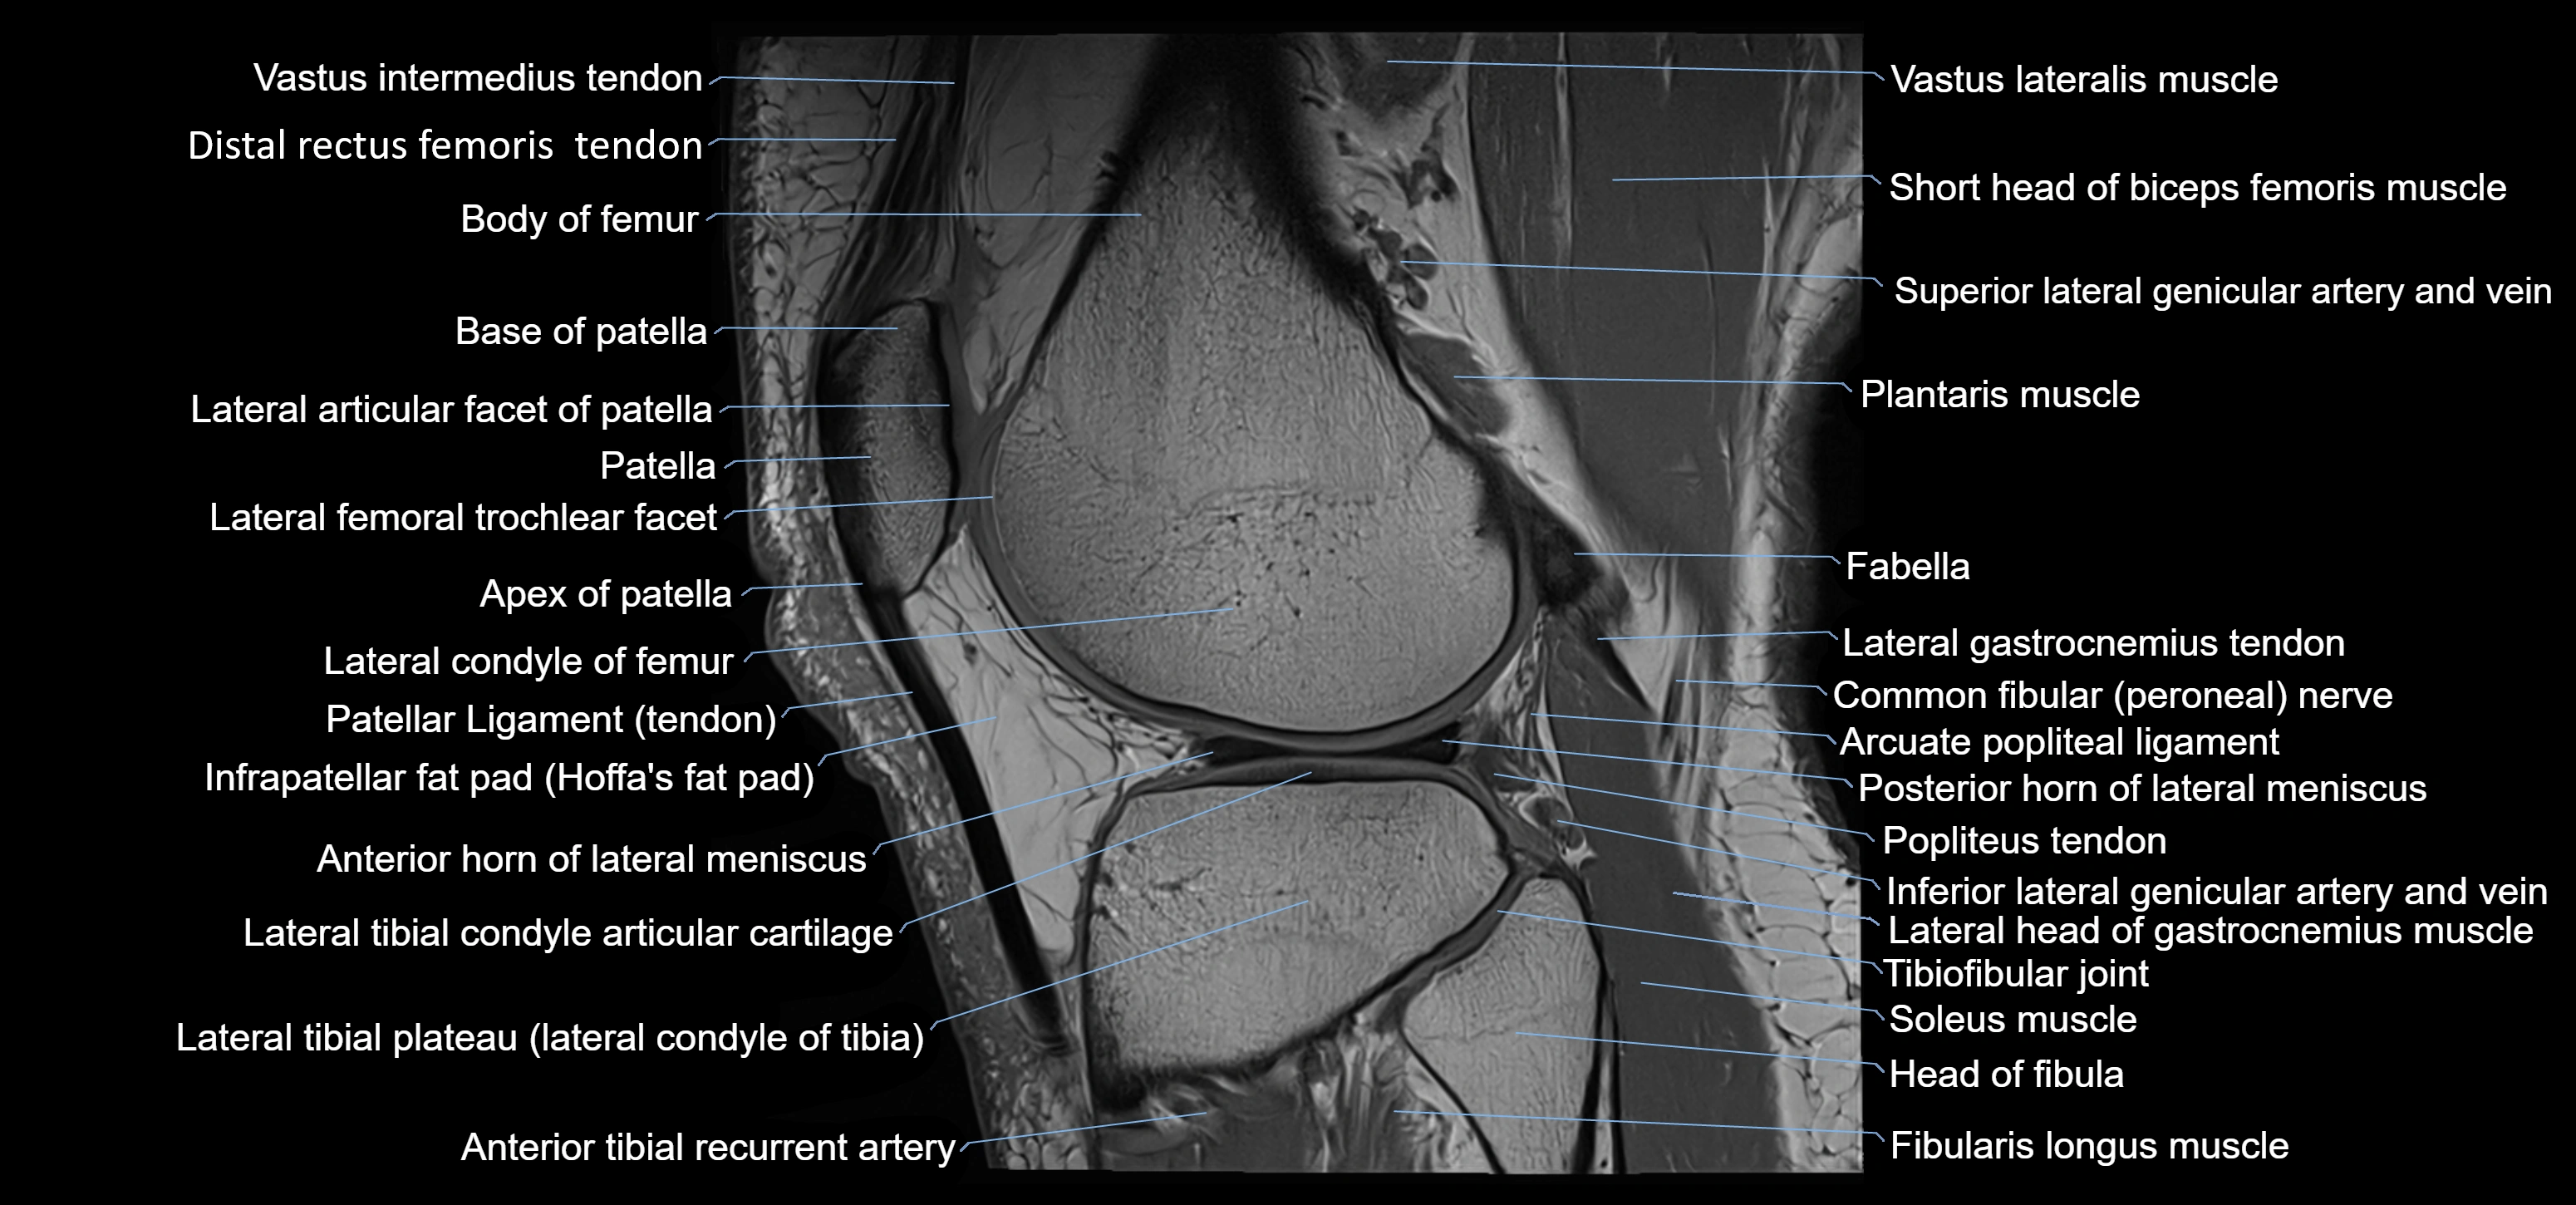

- Anterior horn of lateral meniscus

- Apex of patella

- Base of patella

- Body of femur

- Distal rectus femoris tendon

- Distal vastus intermedius tendon

- Fibularis longus muscle (peroneus longus muscle)

- Head of fibula

- Infrapatellar fat pad

- Lateral articular facet of patella

- Lateral condyle of femur

- Lateral gastrocnemius tendon

- Lateral head of gastrocnemius muscle

- Lateral meniscus

- Lateral tibial plateau

- Neck of fibula

- Patella

- Patellar tendon (patellar ligament)

- Plantaris muscle

- Popliteus tendon

- Posterior cruciate ligament

- Posterior horn of lateral meniscus

- Soleus muscle

- Superior lateral genicular artery

- Superior lateral genicular vein

- Superior tibiofibular joint

- Tibial condyle articular cartilage

- Tibiofibular joint (proximal)

- Trochlear groove

- Vastus lateralis muscle